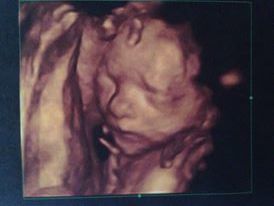

Ahojte dievcata. Tak konecne mam za sebou "velku" poradnu s ultrazvukom a vsetkymi meraniami... Vsetko vyzera byt v poriadku, tak dufam, ze to takto pojde dalej. Akurat sa nam nechcelo otocit zahlavim, takze o tri tyzdne este doktorka chce urobit kratky ultrazvuk kvoli meraniu zahlavia. Boli sme s manzelom stastni, ze vsetko je ako ma byt....tak som si hned vcera kupila jednu rychlozavinovacku.... Inak postielku budem mat od svagrinky + plus nejake vecicky tiez, takze budem kupovat az ked ich od nej zoberiem...podla toho co mi bude chybat... A kocik budem kupovat novy, ale to ma este cas. A baby budete davat ortopedicke nohavicky a balit nasiroko...lebo ze teraz uz sa to moc "nenosi" , ale ja by som chcela.